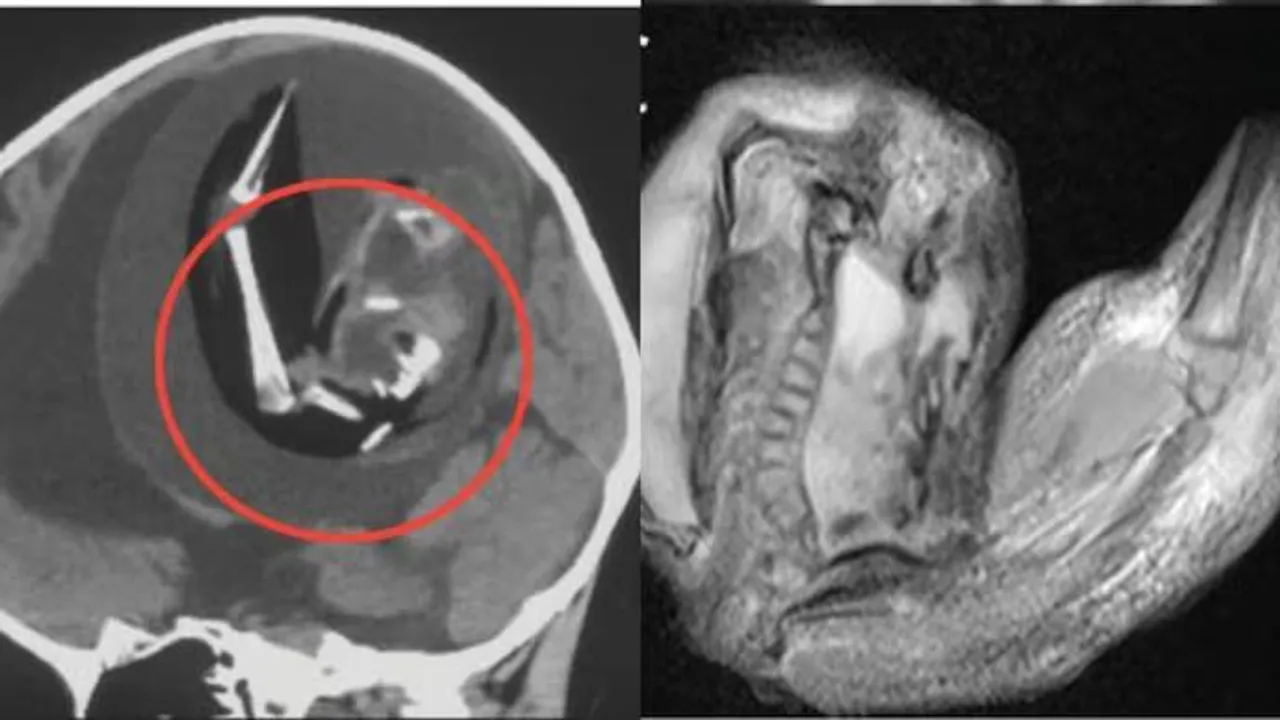

ମୁଣ୍ଡ ବଡ଼ ହୋଇଯିବା ସହିତ କେତେକ କାର୍ଯ୍ୟକଳାପ ପାଇଁ ପିଲାଟିର ମାଂସପେଶୀ କାର୍ଯ୍ୟ ନ କରିବାରୁ ତାକୁ ଡାକ୍ତରଙ୍କ ପାଖକୁ ଅଣାଯାଇଥିଲା। ତା’ର ମୁଣ୍ଡ ସ୍କାନ୍ କରାଯିବା ପରେ ଜଣାପଡ଼ିଲା ଯେ, ତା’ର ମସ୍ତିଷ୍କ ଭିତରେ ଜନ୍ମି ନ ଥିବା ଯାଆଁଳା ଭ୍ରୂଣ ରହିଛି। ଏହାଛଡ଼ା, ସେ ଭ୍ରୂଣ ଦୁଇଟିରେ ଶରୀରର ଉପର ଅଙ୍ଗପ୍ରତ୍ୟଙ୍କ ବିକଶିତ ହେବା ସହିତ ହାଡ଼ ଓ ଆଙ୍ଗୁଠି ଭଳି କଢ଼ି ସବୁ ଗଜୁରି ଥିଲା।

Image Courtesy of India Todayଉକ୍ତ ଭ୍ରୂଣ ଦୁଇଟିର ଗୁଣସୂତ୍ର କ୍ରମ ନିରୂପଣ କରିବା ପରେ ଜଣାପଡ଼ିଲା ଯେ, ସେ ଭ୍ରୂଣ ଅବସ୍ଥାରେ ଥିବା ପିଲା ଦୁଇଟି ମଧ୍ୟ ଏହି ପିଲାର ଯମଜ। ଡାକ୍ତରୀ ଭାଷାରେ ‘ଫେଟସ୍-ଇନ୍-ଫେଟୁ’ ଅବସ୍ଥାରେ ଏଭଳି ଘଟିଥାଏ। ସାଧାରଣରେ ଏହାକୁ ଗୋଟିଏ ପିଲାର ଭ୍ରୂଣରେ ଆଉ ଏକ ଭ୍ରୂଣ ପରି ଦିଶୁଥିବା ମାସଂ ଟିସ୍ୟୁ ଜମିବା କହନ୍ତି।